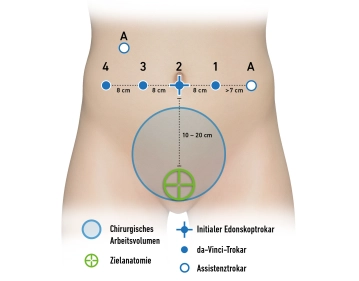

- Para procedimentos mais longos, aplicação de manguitos de compressão pneumática para as pernas para profilaxia de trombose